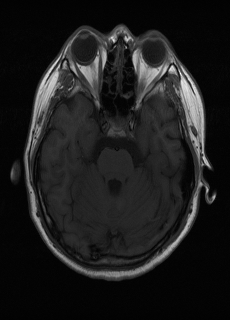

As we observe from the right image in Fig. 2, our BRM, both from MIMO and SISO settings, predicts the performance of dedicated models with a high correlation. We further choose the best three , and perform the last stage of fine-tuning accordingly to (6). A visual evaluation on real data is shown in Fig. 3. For simulated data, please refer to the Supplemental Material section.

Base on the best performing , we perceive that among , , and FLAIR, the results are best when is sampled the most. We suggest that this makes intuitive sense as images provide the best contrast out of the three sequences, which can compensate for the details lost in other images. The same observation can be made on the simulated data, where both and FLAIR show good contrast. When the time setting is changed to non-uniformity, we can see that our search for the best sampling strategy reflects the change. is sampled more as a result of faster acquisition time, while is still sufficiently sampled.

| Sequence | LR | SISO | MIMO | MIMO tuned | GT |

|---|---|---|---|---|---|

(a) 34.38/0.9371

(a) 34.38/0.9371

|

(b) 42.42/0.9883

(b) 42.42/0.9883

|

(c) 44.60/0.9920

(c) 44.60/0.9920

|

(d) 45.50/0.9940

(d) 45.50/0.9940

|

(e) PSNR/SSIM

(e) PSNR/SSIM

|

|

(f) 29.74/0.8903

(f) 29.74/0.8903

|

(g) 36.25/0.9734

(g) 36.25/0.9734

|

(h) 36.42/0.9752

(h) 36.42/0.9752

|

(i) 37.70/0.9832

(i) 37.70/0.9832

|

(j) PSNR/SSIM

(j) PSNR/SSIM

|

|

(k) 39.89/0.9311

(k) 39.89/0.9311

|

(l) 43.94/0.9864

(l) 43.94/0.9864

|

(m) 44.74/0.9883

(m) 44.74/0.9883

|

(n) 45.49/0.9894

(n) 45.49/0.9894

|

(o) PSNR/SSIM

(o) PSNR/SSIM

|